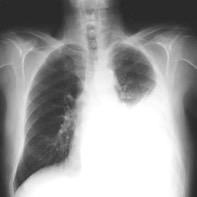

Hematoma pleural después de cateterismo.

Rotura de aneurisma de arteria subclavia Aneurisma “deshinchado” Hemotórax

Fallece en el acto de tomar esta radiografía. La mayoría ateroescleróticos. Más frecuente a la derecha.La rotura: 32-47% de las muertes.

Sun J et al. Isolated True Subclavian Aneurysm without Aberrant Subclavian Artery or Coarctation of Descending Aorta. Annals of Vascular Surgery 2021